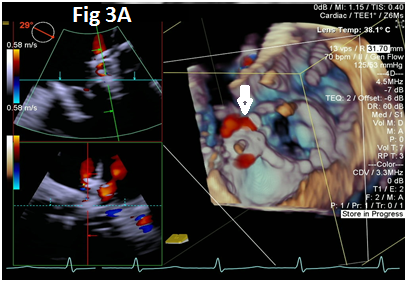

A 73-year-old female with mechanical mitral valve, tricuspid annuloplasty (32mm Edwards Physio Tricuspid incomplete ring) underwent Transcatheter Tricuspid Valve Replacement (TTVR) using off-label 29mm Edwards Sapien 3 (S3) Transcatheter Heart Valve (THV). Immediate post valve deployment, mild Perivalvular Leak (PVL) was noticed at the septal aspect (area of incomplete annuloplasty ring). Eighteen months later, patient presented with recurrent right heart failure and paracentesis due to severe tricuspid PVL (Figure 1A-C, Video 1). Percutaneous PVL closure under general anesthesia, Trans-esophageal Echocardiography (TEE) was performed. Via femoral venous access, defect was easily crossed with Agilis steerable sheath, multipurpose catheter and 0.035” glide wire. Despite recurrent attempts, wire came through the PVL but then traversed through open cells of S3 into the right ventricle (Figure 2A), confirmed with Armada 6mm balloon waist at the S3 cage (Figure 2B) (despite inflating 28mm Z med balloon inside S3 cage, Figure 2C). We decided to partially deploy the plug and assess valve function. Using 7.5F Asahi Eaucath multipurpose guide, a 12mm AmplatzerTM Vascular plug II (AVP II) was advanced through the defect. The ventricular disc was opened inside the S3 cage while body in the PVL defect (outside the S3 cage) and atrial disc on the atrial side of PVL (Figure 3A-B). With S3 function unaffected, no central leak and minimal gradient, PVL reduced to mild severity (Figure 4A-D, Video 2); the AVP II was successfully deployed (Figure 5). At 3-month follow up, there was an excellent symptomatic improvement (NYHA functional class I), with no heart failure re-hospitalization or paracentesis. Deployment of plug disc inside the valve frame is not recommended due to fear of interference with leaflet function and possible injury in long term. There was no immediate issue with the valve function in this case (due to space between the leaflet and frame of S3 and depends on size of plug used). Valve-in-Valve (S3-in-S3) would have certainly sealed all open cells treating this PVL but is more expensive option.

Figure 1 Para-valvular leak shown by color Doppler (1A) on 2D and 3D (1B) images, along with dense tricuspid spectral Doppler signal with peak velocity of 3m/s (1C).